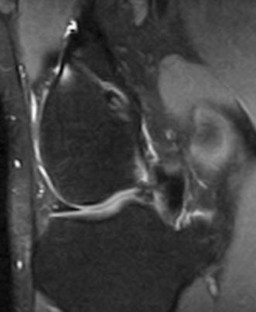

Tunnel enlargement after anterior cruciate ligament (ACL) reconstruction may compromise revision surgery. The cause of this tunnel enlargement is not yet fully understood, but it is thought to be multifactorial, with biomechanical and biological factors playing a role. Tunnel enlargement has been described particularly in patients who underwent ACL reconstruction with hamstring tendons with extracortical fixation devices. The purpose of our study was to evaluate prospectively with magnetic resonance imaging (MRI) the changes in femoral tunnel diameter following arthroscopic anatomic ACL reconstruction with hamstring tendons. At 3-month post-op, all tunnels had enlarged compared to the diameter of the drill and most tunnels enlarged more in the midsection than at the aperture. In the posterolateral tunnels, the entrance increased 16% in diameter and the middle of the tunnel increased 30% in diameter. In the anteromedial femoral tunnels, the tunnels enlarged 14% at the aperture and 35% in the midsection. All femoral tunnels enlarged and most of them enlarged in a fusiform manner. The biological factors explain better our findings than the mechanical theory, although mechanical factors may play a role and the cortical bone at the entrance of the tunnel may modify the way tunnels respond to mechanical stress.

Fig. 2